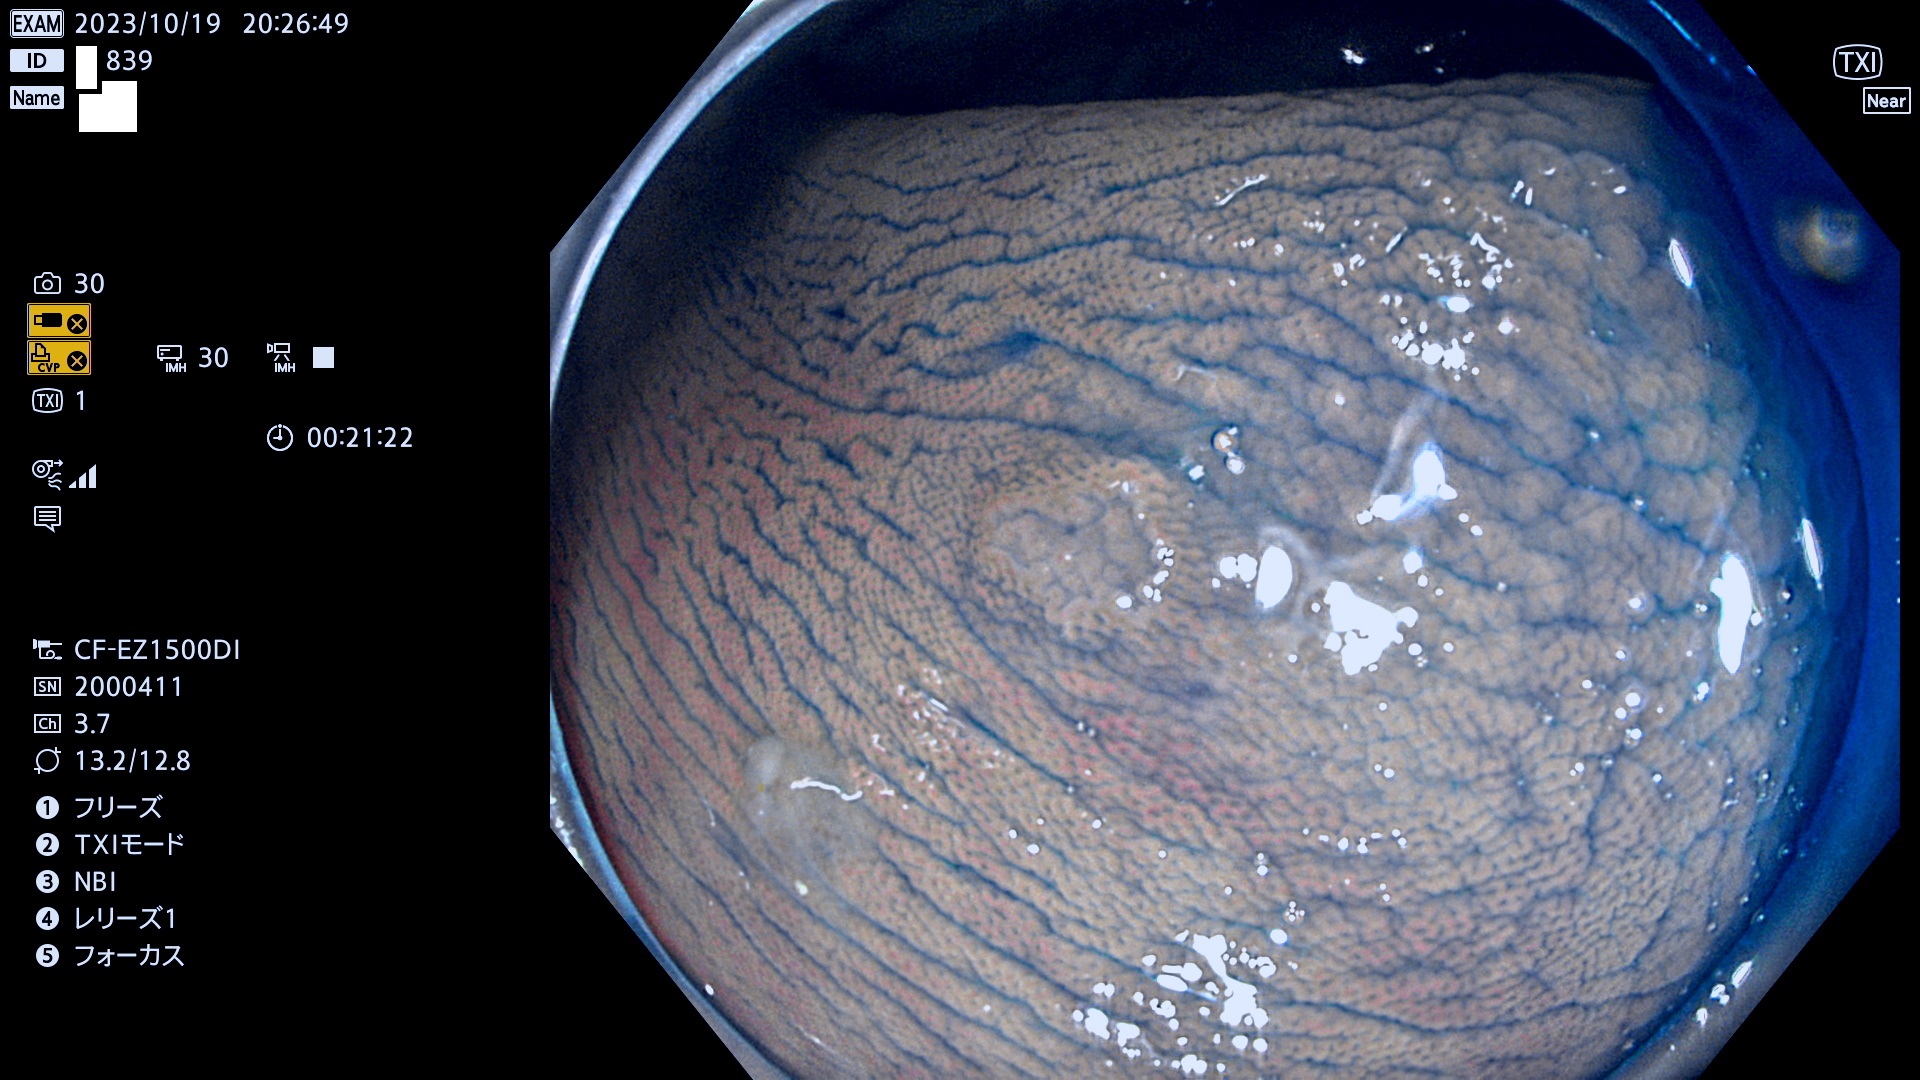

抽出の対象期間 2023年10月19日(木)〜10月22(日)の4日間(48件の検査)5件

炎症(ビラン)と鑑別の困難なUc型腺腫の例